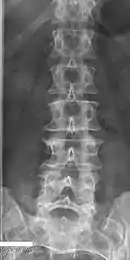

Lumbarization of sacral vertebra 1, seen as 6 vertebrae that do not connect to ribs.

Sacralization of the L5 vertebra is seen at the lower right of the image.